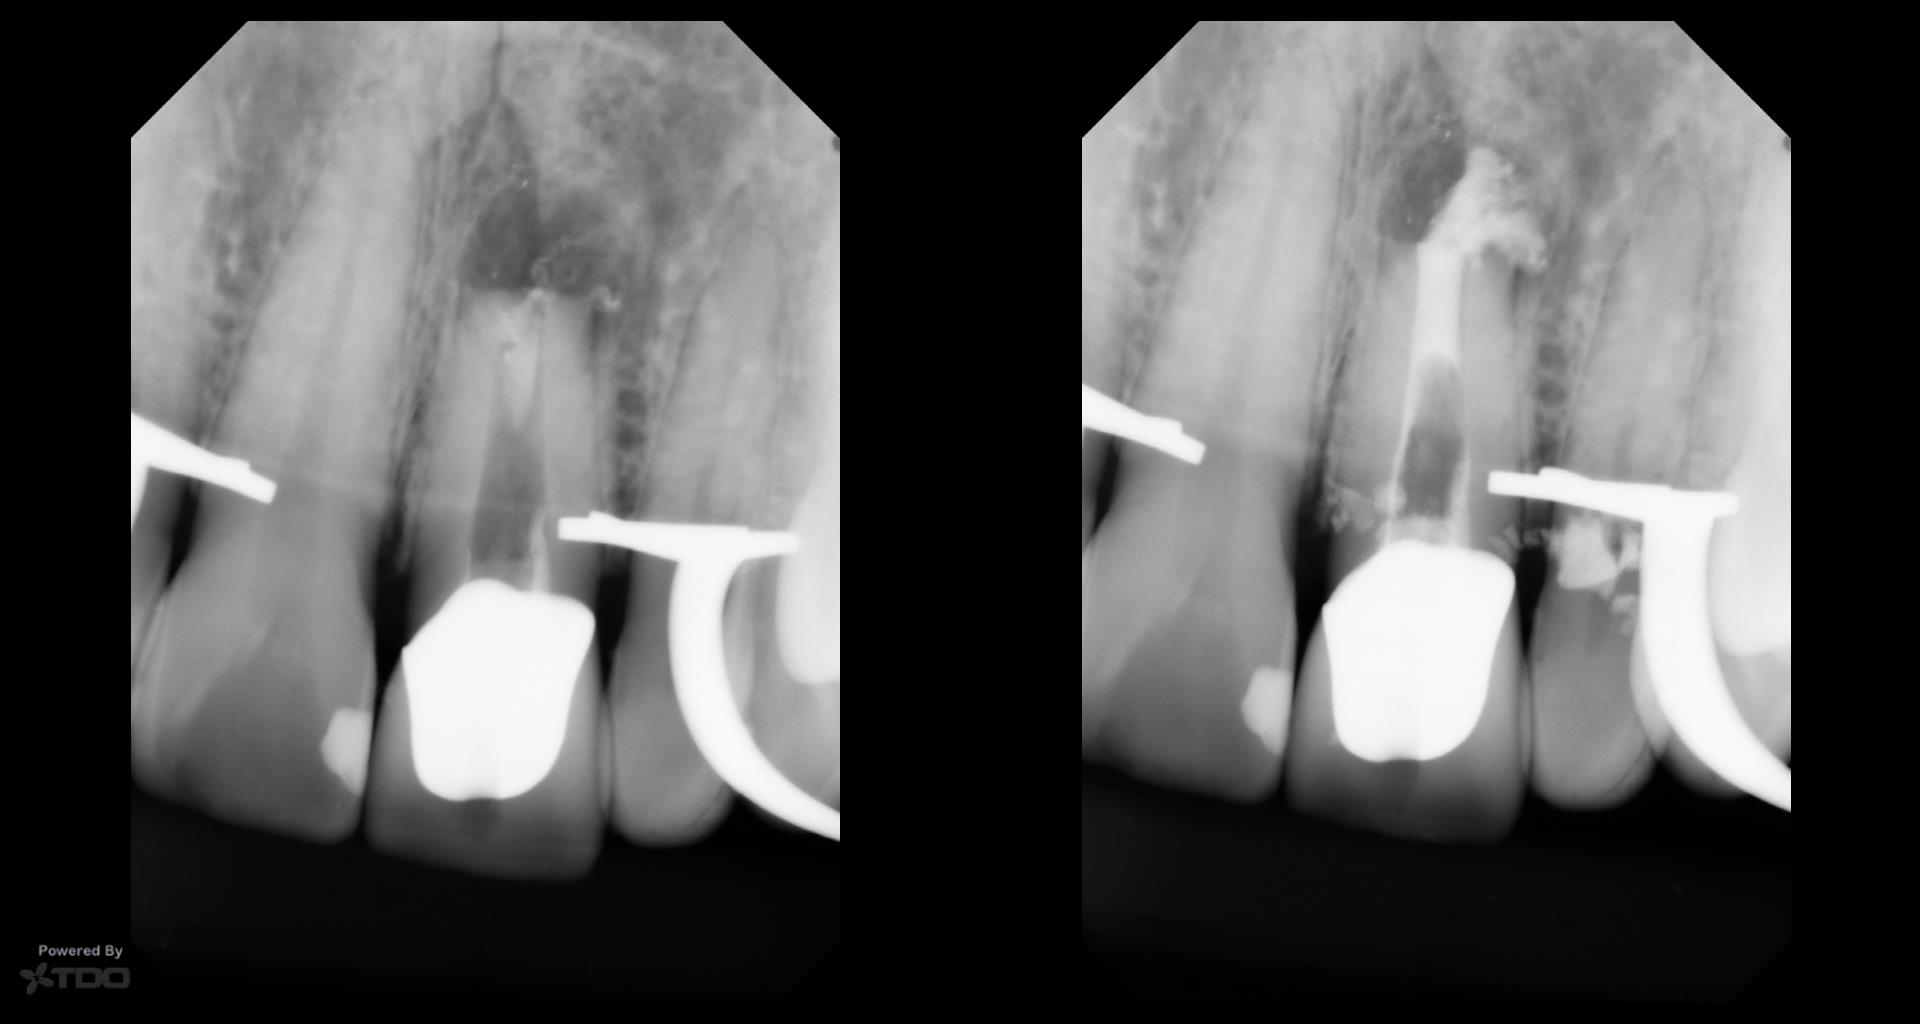

This was interesting because a root frac ture was seen where the prior apico was done. The MTAS was removed and Brassler putty used in this case. Will take a 1 yr CBCT and we will know more. Don’t usually get so much scar formation–so this was surprising…..